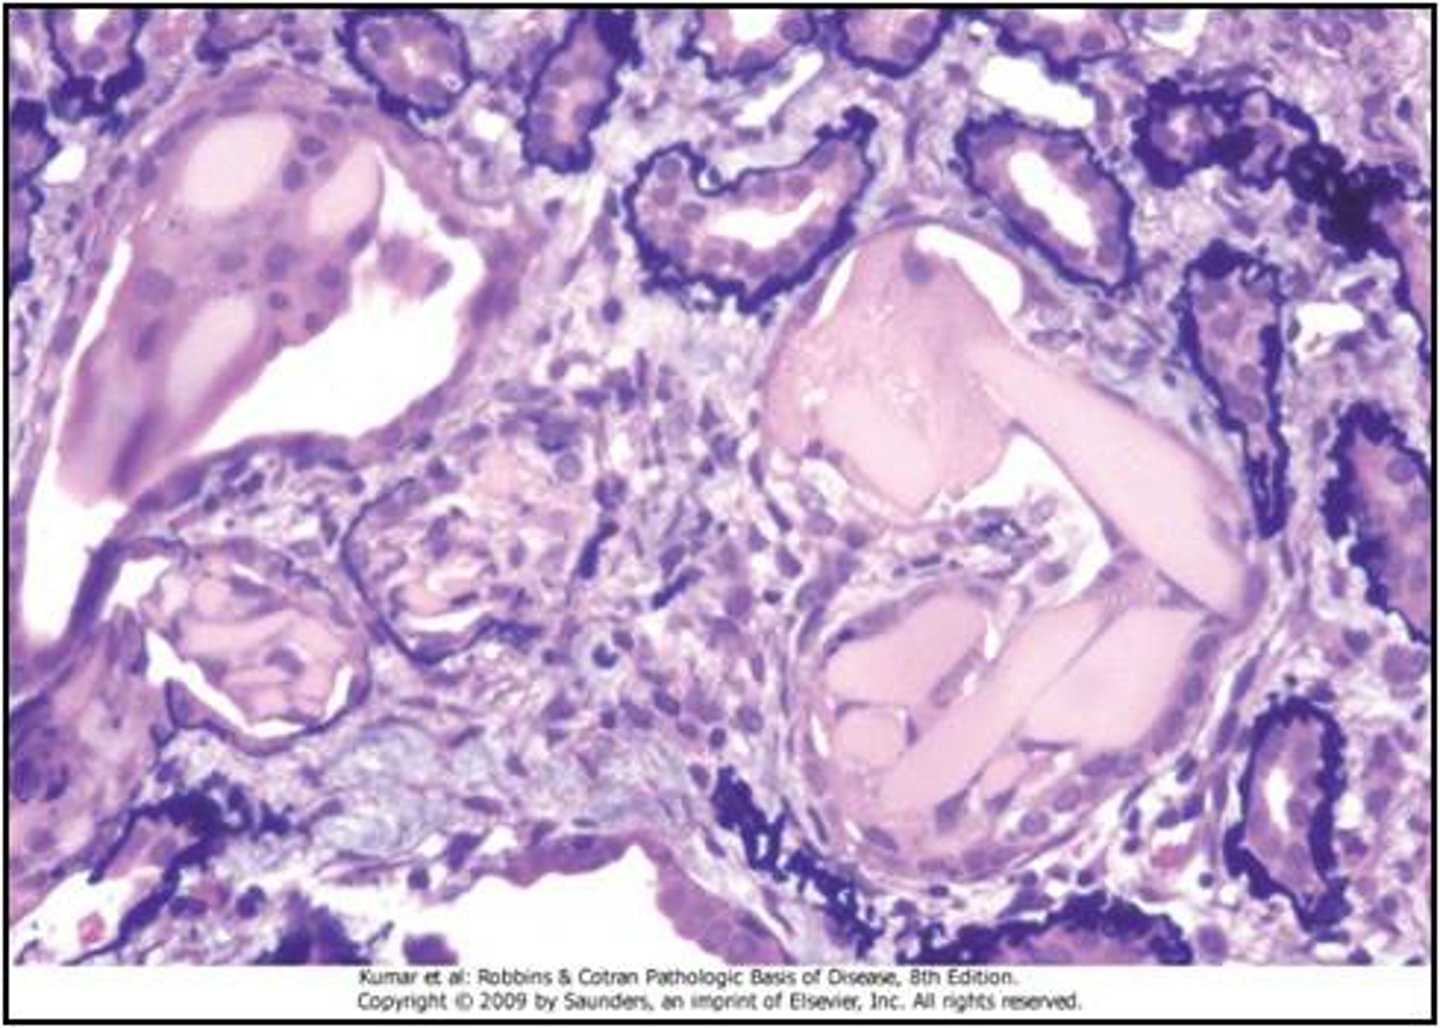

nodular glomerulosclerosis

granular deposits are present on glomerular basement membrane, mesangium and tubular basement membranes

kidney biopsy finding associated with LCDD